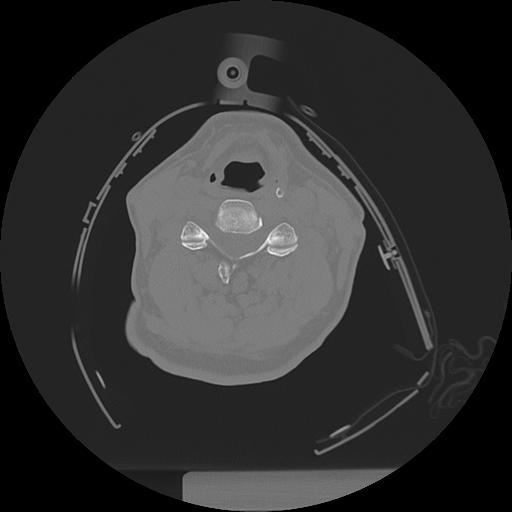

11 HUESO,,Axial,2.0,HUESO,,